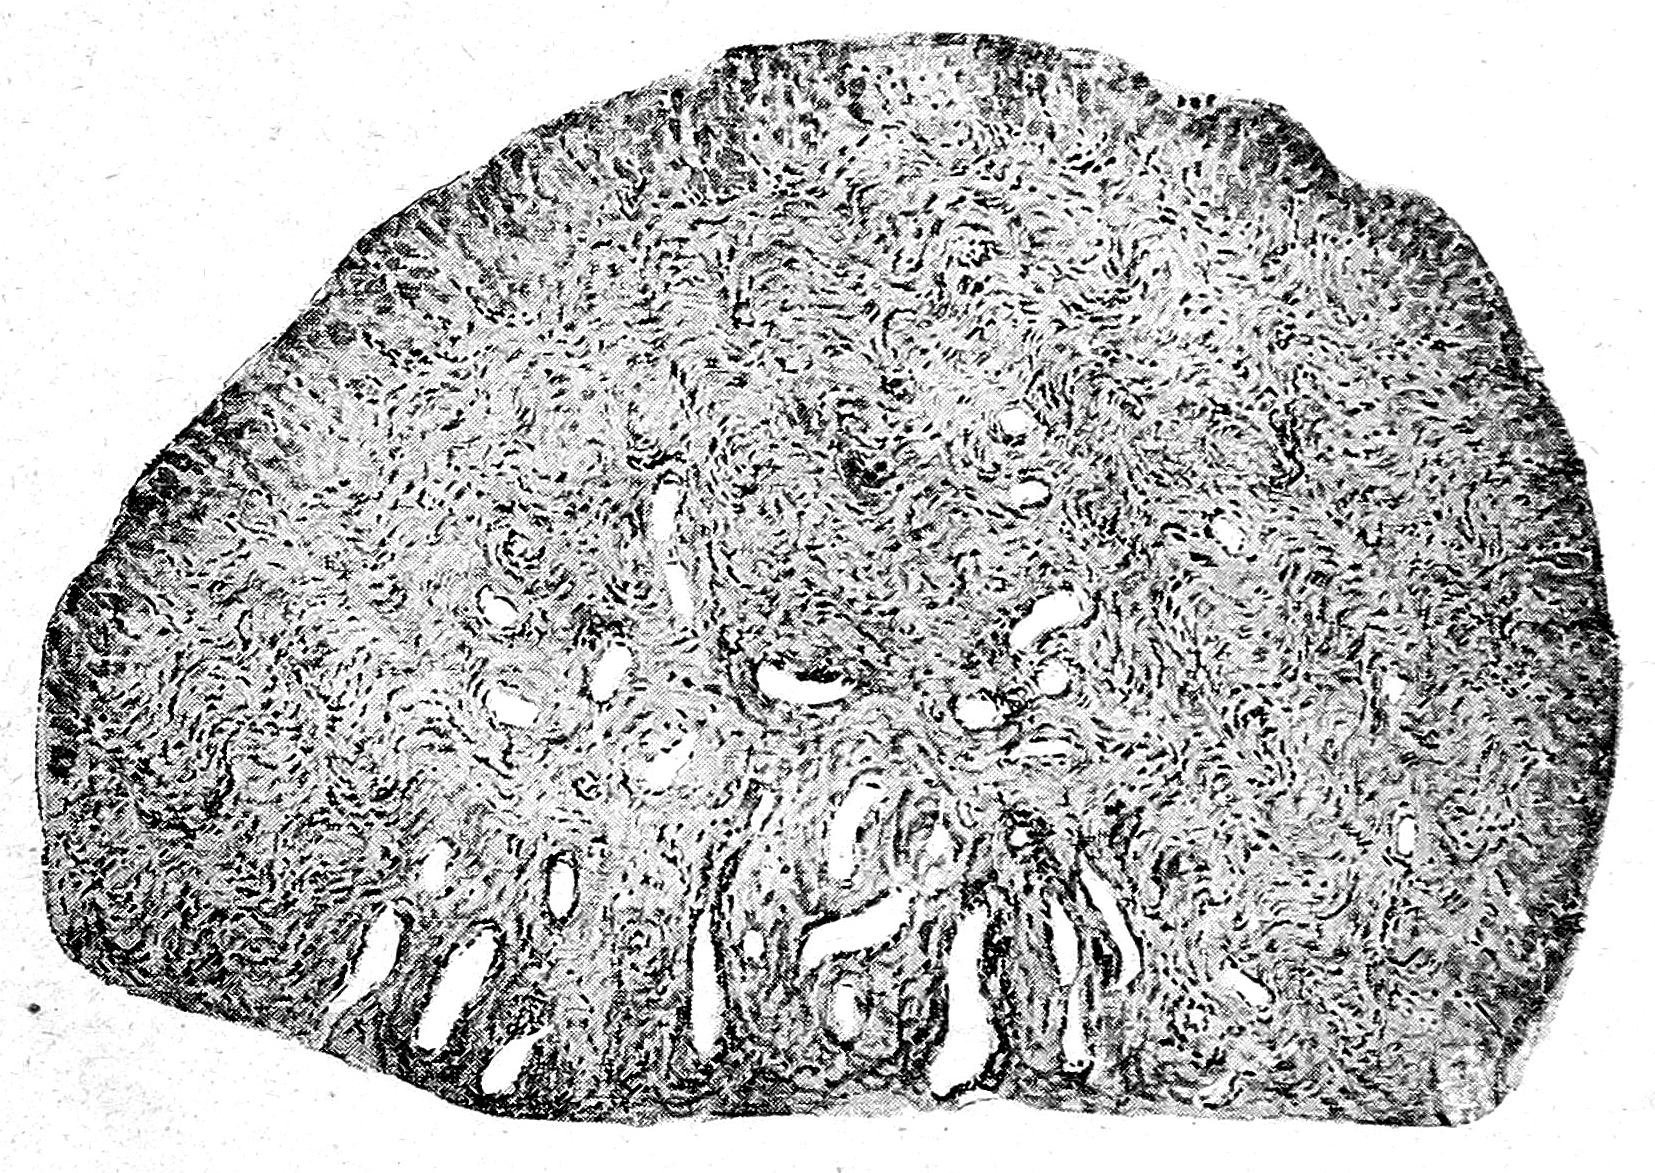

Яичник (рис. 2). Казавшаяся макроскопически гладкою поверхностъ яичника под микроскопом оказалась представляющею значительное количество выпуклостей и углублений. Зародышевый эпителий сохранился местами лишь в этих последних, на большей же части поверхности яичника он вероятно, отслоился при консервировании препарата. Клетки эпителия оказались гораздо более низкими, чем нормально, почти пластинчатыми. Под эпителием располагалась отчетливо выраженная в виде сравнительно бедного клетками слоя волокнистой соединитель той ткани tunica albuginea от которой вглубь подлежащей яичниковой стромы отходили, в радиальном направлении фиброзные перегородки. Располагавшиеся между этими перегородками участки стромы коркового слоя состояли из типичных для последнего веретенообразных клеток, среди которых было заложено значительное количество кровеносных сосудов мелкого калибра. Напротив, ни отчетливо выраженных примордиальных фолликулов, ни каких-либо остатков более зрелых фолликулов, в виде, напр. Glasmembranen corpora albicantia и т. п., в корковом слое, несмотря на самые тщательные поиски, обнаружить было нельзя. Кнутри от коркового слоя располагался богатый более крупными сосудами мякотный слой, строма которого состояла из плотной, бедной ядрами соединительной ткани.

Рис. 2.